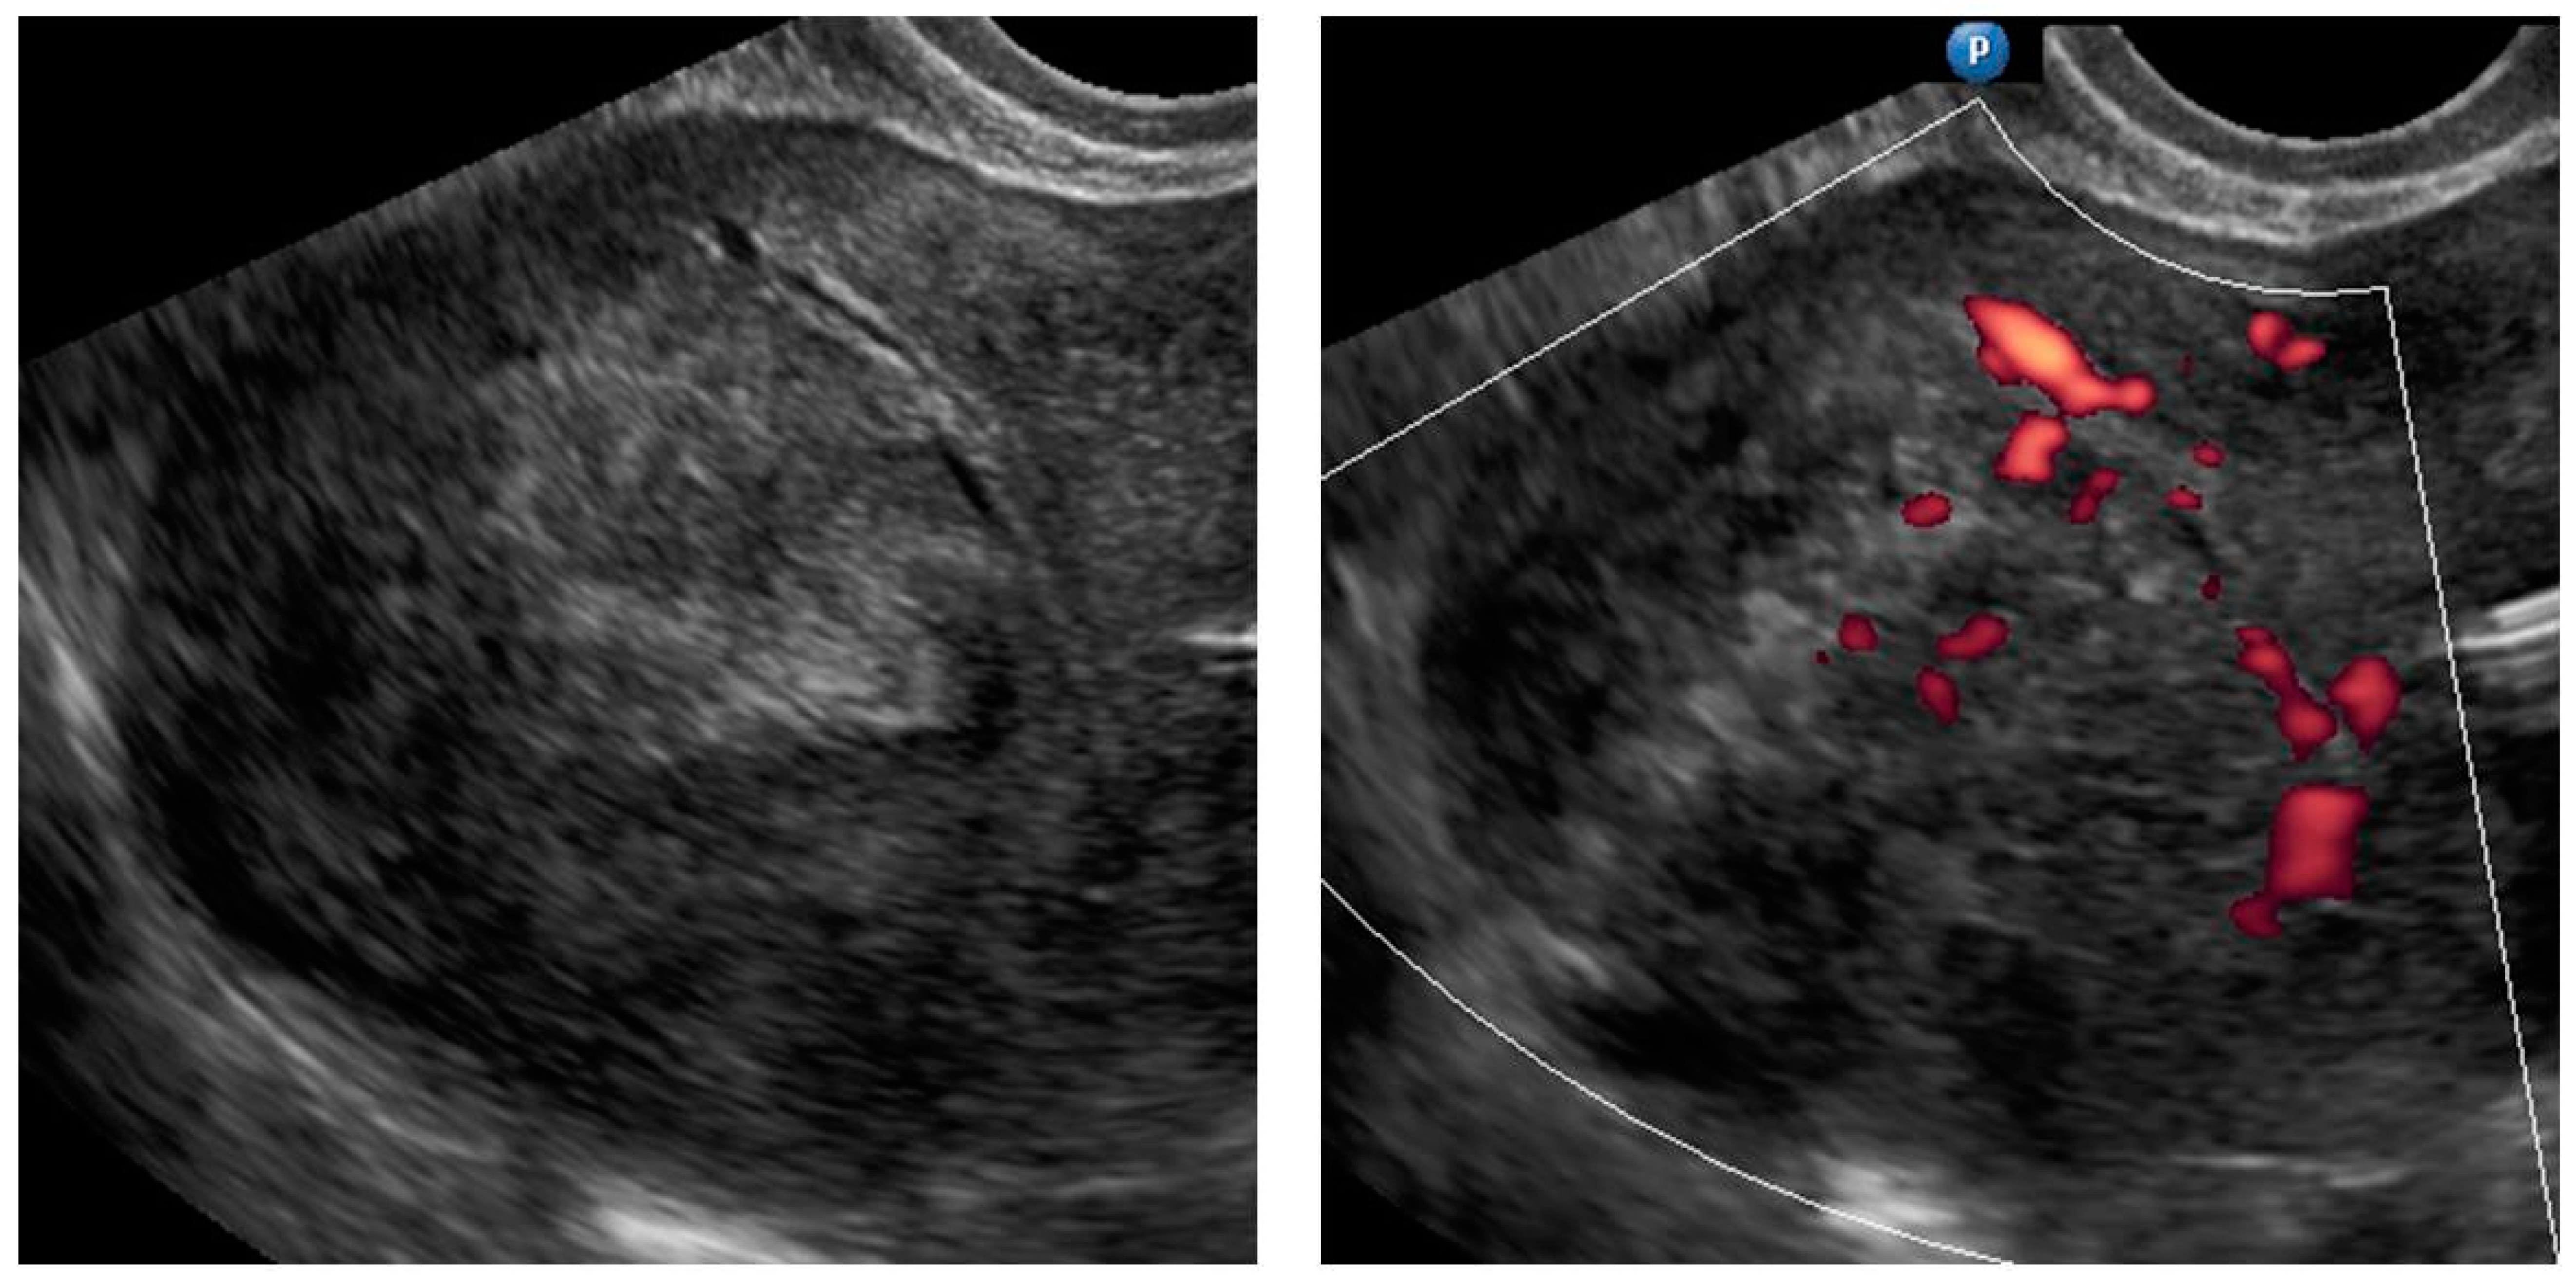

| 5 (50) | Atypical uterine lesion (metastatic adenocarcinoma G3 in inguinal lymph node) | Figure A5 | Yes | No | Leiomyoma (UG-TUC core needle biopsy) | No | Uterus / tumor not resected because primary urological carcinoma was diagnosed | Yes | Yes |